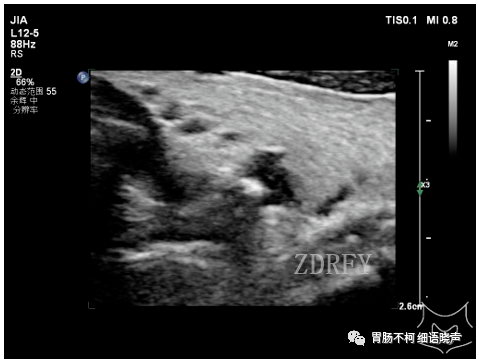

病例一:甲状腺左叶后方低回声型咽食管Killian-Jamieson憩室。

其后方与食管相通。

吞咽口水实验可见团块状强回声涌入。